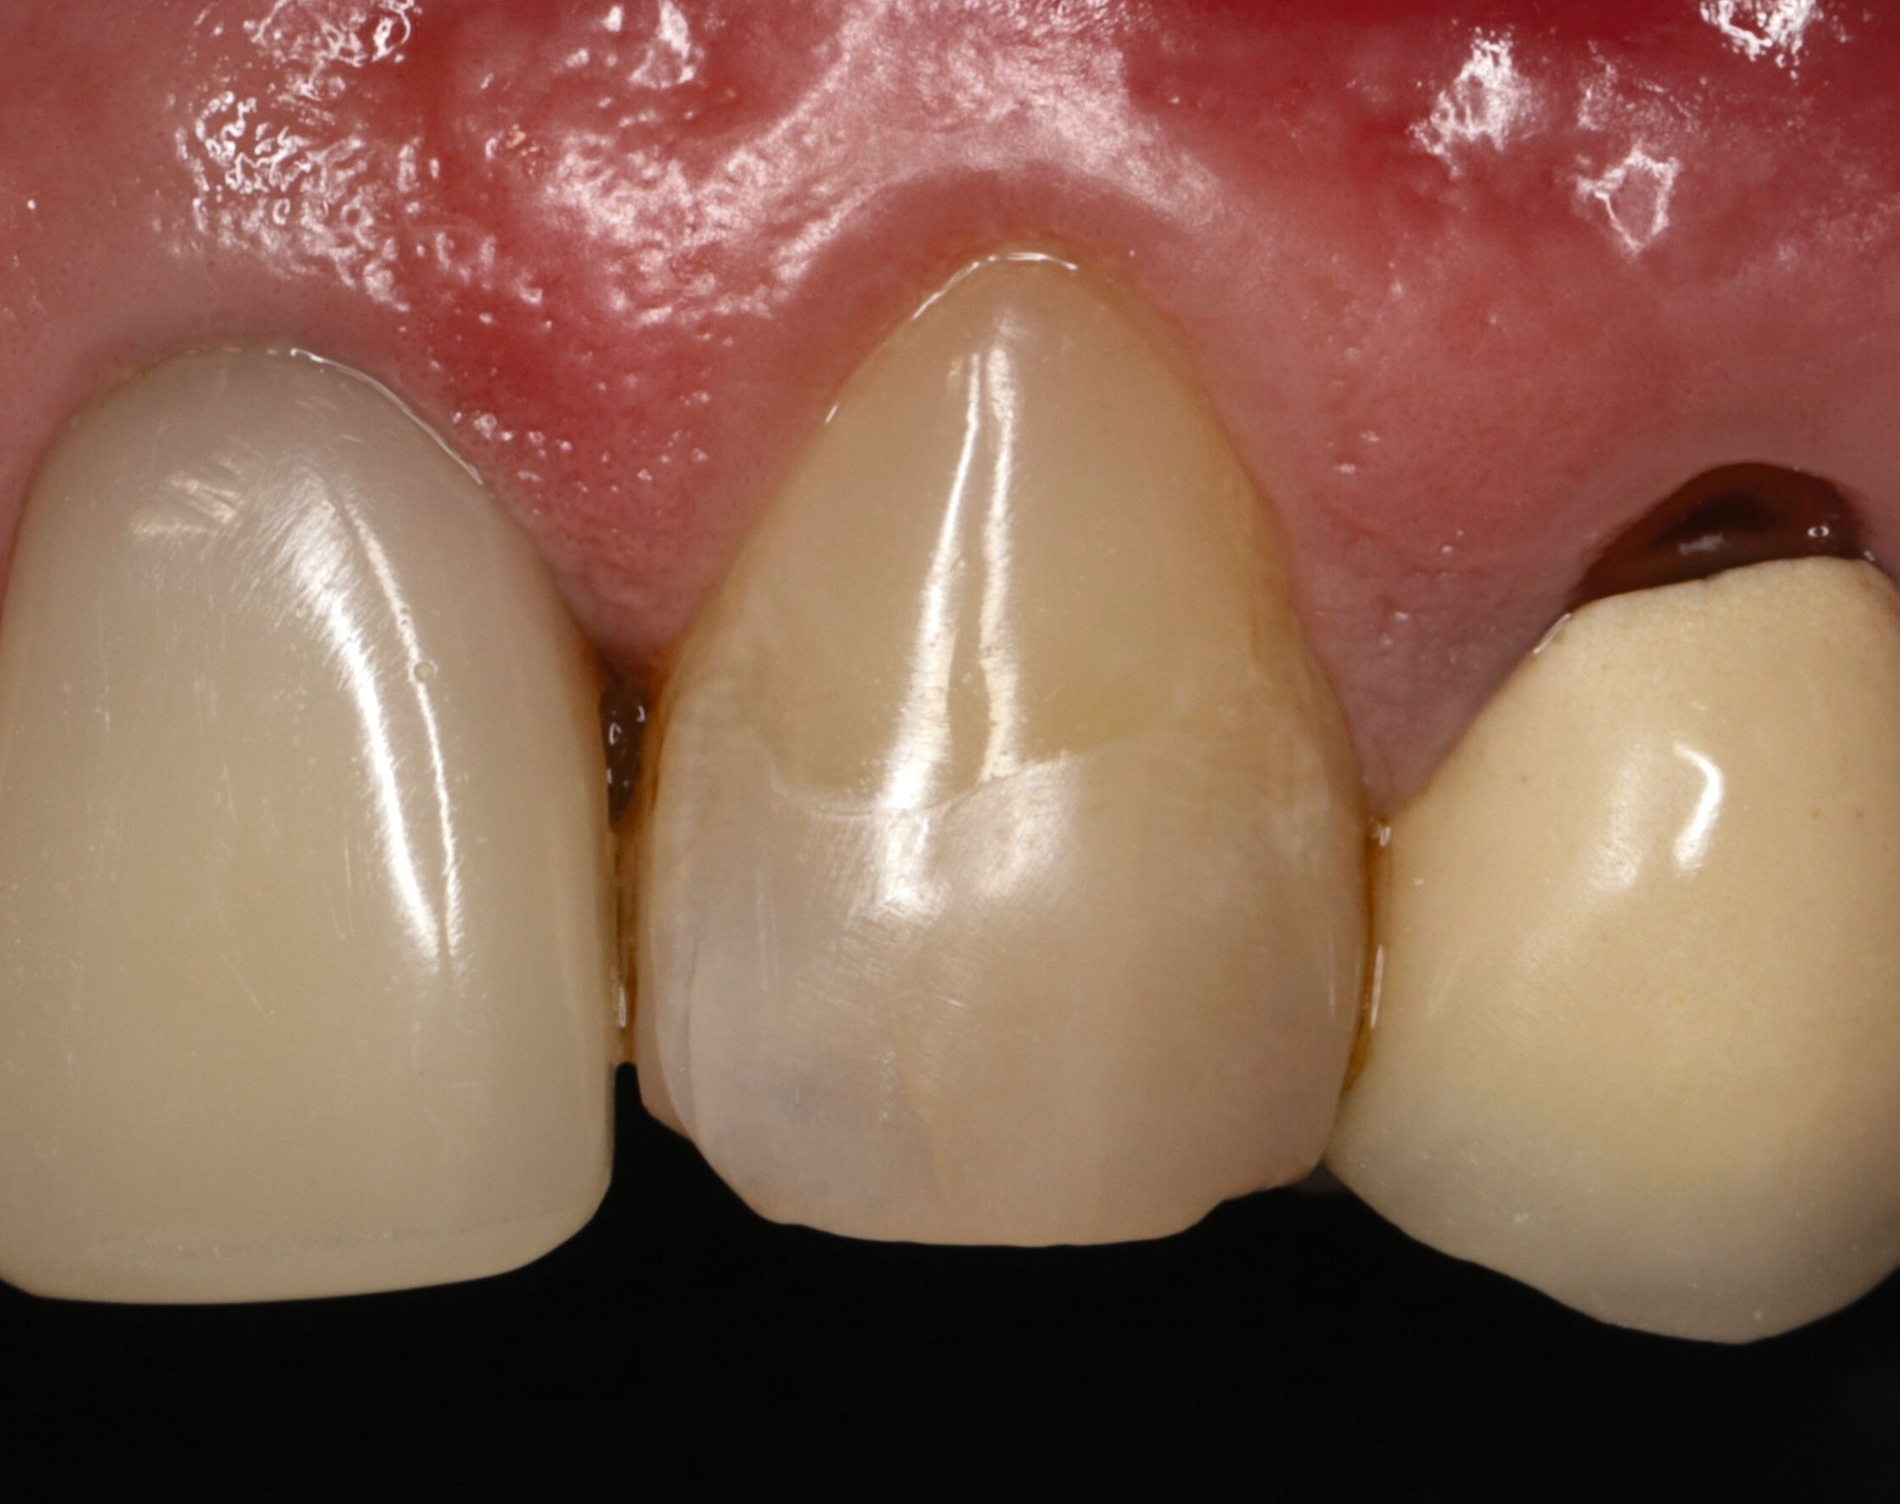

Für die restaurative Therapie von Zahn 22 wurde die alte Stiftkrone entfernt und die Stiftbohrung an die neue Indikation angepasst (Abbildungen 5a und 5b). Die Zahnkrone wurde dabei in drei Phasen wiederhergestellt: adhäsives Zementieren eines konfektionierten Glasfaserstifts, Stumpfaufbau und Modellation einer direkten Kompositkrone mit Silikonschlüssel, Frontzahnmatrize für komplexe Situationen und Schneepflugtechnik (Abbildungen 5c bis 5e) [Urkande et al., 2023; Amaro et al., 2021; Frese, 2020; Mannocci et al., 2002; Dimitrouli et al., 2011; Opdam et al., 2003]. Im Röntgenkontrollbild zeigt sich ein suffizienter Stiftaufbau (Abbildung 6).

Der klassische Erosionsdefekt mit einem schmalen, zervikal gelegenen, intakten Schmelzrand sowie einer plaquefreien Oberfläche an Zahn 23 wurde mit einer direkten Kompositrestauration nach Legen eines Retraktionsfadens therapiert (Abbildung 8).